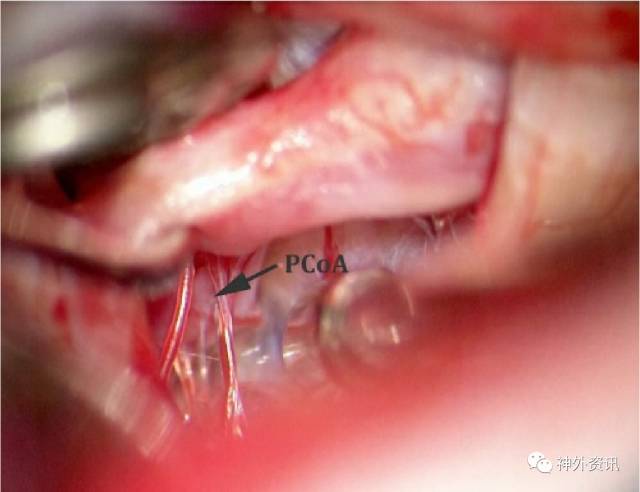

图16:一旦建立可靠的近端ICA控制,常常可沿着ICA的内侧缘,向远离术者的方向,找到PCoA远端。在视神经颈内动脉三角内可见PCoA动脉及其穿支。

图17:PCoA的起始部往往只能看到一个小凸起,在动脉瘤囊正下方(见上方手绘图)。动脉瘤永久夹最终就是放置在这个小凸起(箭头,下图)和真正的动脉瘤颈之间。在接下来动脉瘤颈分离步骤中,通常需要应用临时阻断夹,尤其是对于破裂动脉瘤。

动脉瘤囊和PCoA沿远离术者方向走行。因此,只能看见一个代表PCoA起始部的小凸起。笔者比较喜欢短暂临时阻断ICA近端;如果Willis环功能存在,我不认为临时阻断期间应用依托咪酯是必要的。在高风险操作过程中,减少动脉瘤充盈可显著加快其瘤颈的分离。

在这个凸起和动脉瘤颈近端之间继续分离瘤颈,并沿ICA外侧缘继续向远侧分离。虽然这个操作可能很乏味,但在高倍放大下锐性分离几乎总是能在PCoA和动脉瘤颈之间找到界面。